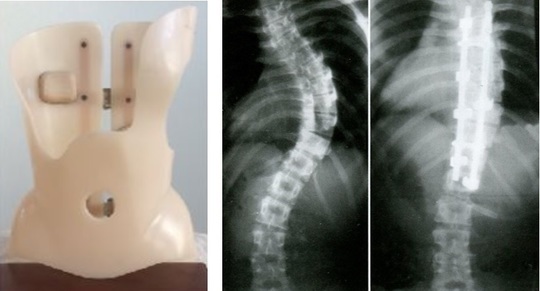

ゲンシンゲン装具

ゲンシンゲン装具は東京(麹町)のシュロスベストプラクティスジャパンが日本で唯一の輸入代理店になる側弯症の装具です。

ゲンシンゲン装具と従来の装具の大きな違いは、ゲンシンゲン装具では 側方の変形 のみでなく、 前後方向(腰椎前弯の改善) 、 回旋(ねじれ) の矯正も強力に 可能です。そのために非常に強い矯正力を得ることができています。

改善例1

改善例2

シュロス法の ゲンシンゲン装具を装着した画像です。カーブの角度が明らかに改善していることがわかります。

カーブタイプによっては改善例2のようにショートタイプの装具でも十分に矯正が可能です。

従来の側弯症治療では手術以外にカーブの変形を改善することは難しいと言われていますが、このゲンシンゲン装具とシュロス法の運動療法を併用することで側弯の改善を可能にしています。

ゲンシンゲン装具は世界でも唯一側弯症の改善が可能な側弯症用の装具です。ゲンシンゲン装具についてご検討の方は当院まで一度ご相談ください。